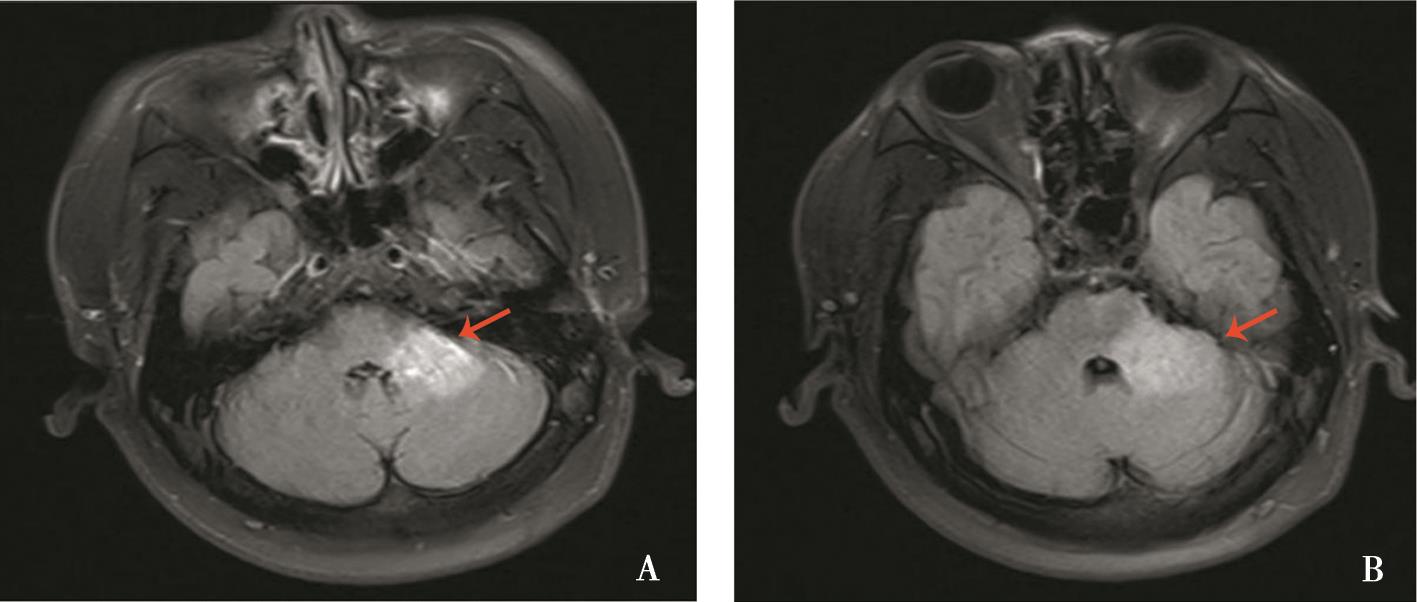

摘要:该文报道了系统性红斑狼疮(SLE)、可能抗磷脂综合征(APS)与视神经脊髓炎谱系疾病(NMOSD)在同一患者体内的重叠表现,并探讨三者可能的关联机制。患者,女性,57岁,病程可分为3个阶段:第一阶段表现为反复血小板减少,伴高滴度抗心磷脂抗体阳性;第二阶段出现双眼视力进行性下降直至失明,眼底检查可见双眼视神经萎缩,视神经磁共振成像(MRI)及脊髓MRI提示脱髓鞘病变;第三阶段则表现为双下肢麻木、皮肤瘀点及多系统受累,免疫学检查证实抗核抗体、抗双链DNA抗体及抗SSA抗体阳性。患者最终确诊为SLE合并可能APS及双阴性NMOSD。该病例显示SLE、APS及NMOSD可能通过免疫紊乱与血管损伤机制相互交织,共同促进疾病的发生发展。临床实践中,对于病程复杂且表现多样的患者,应警惕多种自身免疫病的重叠,结合临床表现、免疫学指标及影像学检查,进行全面评估和早期干预,可能有助于改善长期预后。